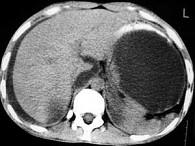

问题 男,33岁,腹部外伤后两月余,腹部疼痛,行CT扫描所见如图,最可能的诊断是 ( )

选项 A.急性胰腺炎 B.慢性胰腺炎 C.胰腺创伤性假性囊肿 D.畸胎瘤 E.腹腔包裹性积血

答案 C